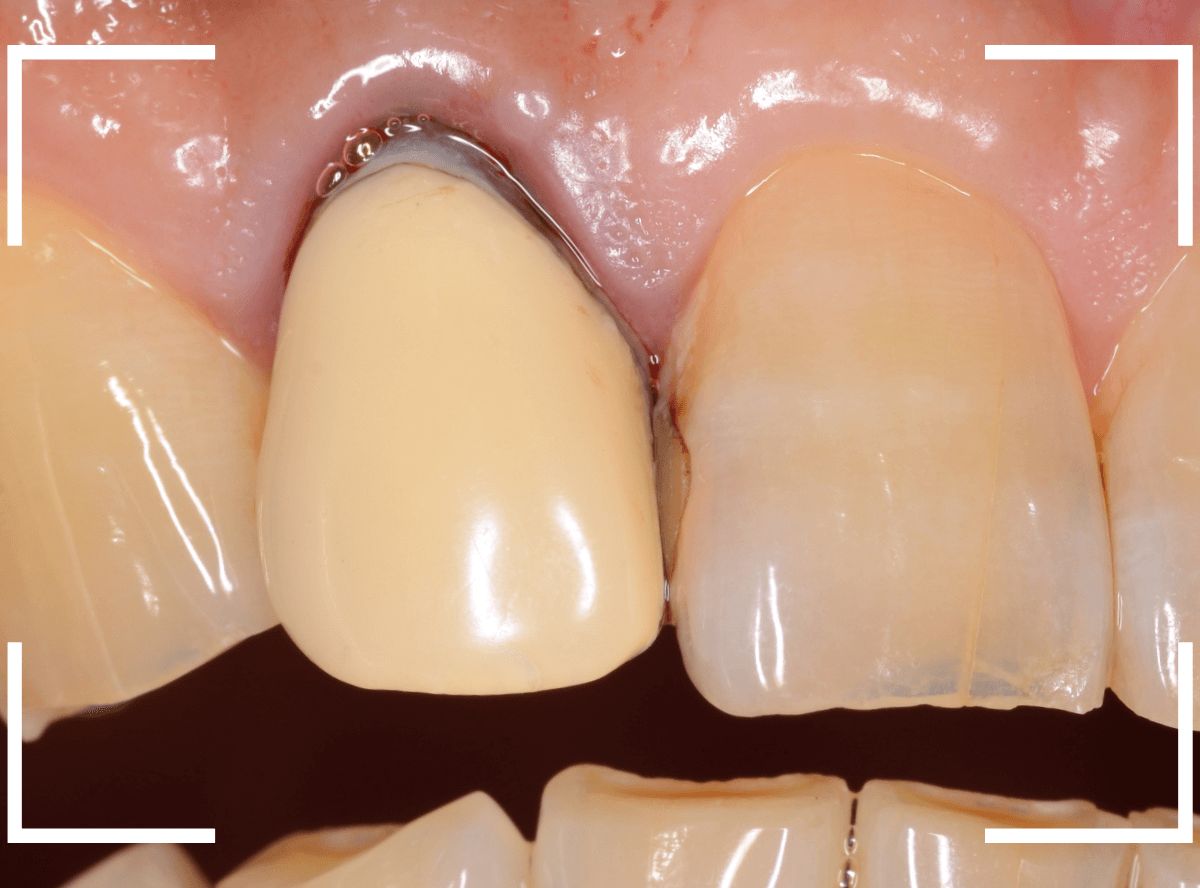

さて、この方の歯の形を確認すると、左右でかなり歯の長さに差があります。

お聞きすると、「若干、そこも気になっていたので、一緒に治療できるならお願いしたい」との事でした。

治療をするためには、歯肉の形をトリミングするなどの若干の外科処置が必要です。

多少の痛みを伴いますが「頑張ります!」との事でしたので、そこも含めて治療する事になりました。

治療のためにさし歯を外すと、隣の歯のレジンの隙間に小さな虫歯が見つかりました。

これはさし歯を外した時あるあるなのですが、一緒に治療をします。

治療をすると、中まで入り込んだ虫歯でしたので、レジンを全て外して治療をし直します。

次に、隣の歯との高さに揃えるために、歯肉をメスで切開して、そこに合わせて歯の形を形成しなおします。

この形に合わせた仮歯を製作し、歯肉が落ち着くまでしばらく経過観察します。

痛みが引き、歯肉の形が整ってきたところで、型をとってさし歯を製作します。

今回は、ジルコニア・セラミックで製作する事になりました。